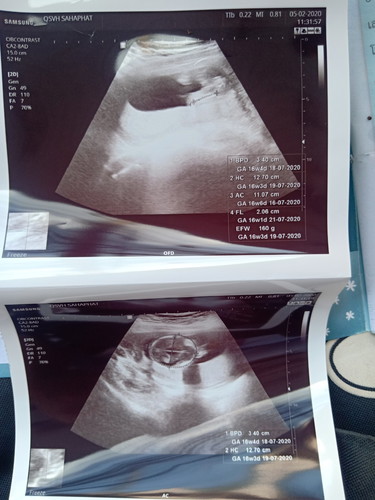

วันนี้ไปหาหมอมาครรภ์พึ่งได้15w แล้วหมอบอกว่าจะผู้ชาย เชื่อได้กี่เปอร์เซ็นต์คะ

หมอฟันธงยังจ๊ะ? ถ้าฟันธงแล้วก็เชื่อหมอจ๊ะ ถ้ายังไม่ฟันธง ก็รอสัก 20 วีคจ้า อวัยวะจะโตพอที่จะคอนเฟิร์มเรื่องเพศได้